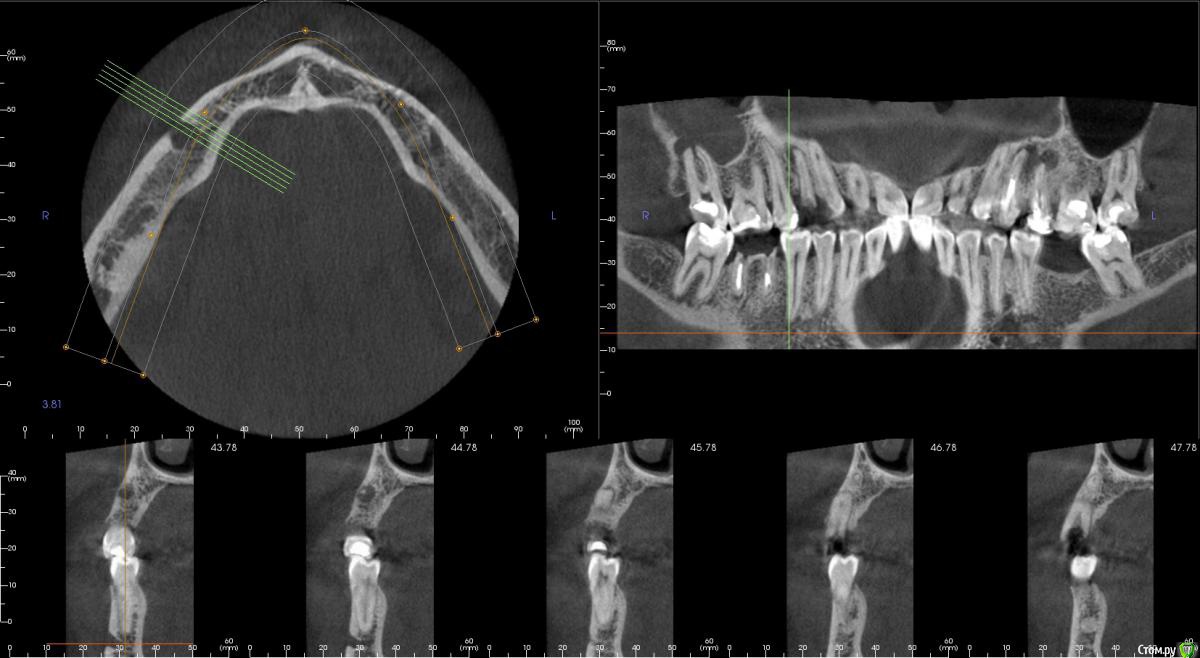

kamranchick Опубликовано 5 ноября, 2015 Поделиться Опубликовано 5 ноября, 2015 Добрый день уважаемые форумчане)Хочу посоветоваться с Вами.Пациент обратился по поводу 14 зуба, хочет удалить и поставить имплантатаБыло предложено идти но одномоментную имплантацию.Вопрос - есть ли противопоказание в данном случае? нужно ли аугментация?Я рассматриваю варианты с устновкой имплантата ALpha Bio SPI 3.3 -13мм, и установка формика с шашлычком(так как бугры хорошие), при условии хорошего торкаВаши советы... Ссылка на комментарий

bullbull Опубликовано 6 ноября, 2015 Поделиться Опубликовано 6 ноября, 2015 Диаметр можно и побольше, как мне кажется. Ссылка на комментарий

kamranchick Опубликовано 6 ноября, 2015 Автор Поделиться Опубликовано 6 ноября, 2015 А удастся ли поставить osstem 3.5 на 11.5, подойдёт ли он для одномоментный? Спрашиваю с целью того, что есть в наличии этот имплантат Ссылка на комментарий

gum Опубликовано 6 ноября, 2015 Поделиться Опубликовано 6 ноября, 2015 Коллега диаметр однозначно больше 3,5 или 3,75, а то что нет в наличии, так закажите. Можно и формик без проблем. Ссылка на комментарий

faity Опубликовано 10 ноября, 2015 Поделиться Опубликовано 10 ноября, 2015 По сути переапикальные изменения обусловленны инфекцией непосредственно в каналах и после удаления причинного зуба, даже при наличии остаточной МО в костной ткани это никак не мешает приживлению импланта.Но к сожалению мои выводы основанны исключительно на литературных данных в этой области, т.к. я не дядя Карен и не имею возможности проводит гистологические исследования По топику: апекс импланта я бы немного вестибулярнее расположил, чтобы шахта выходила на бугры, а не на вестибулярную стенку и по длине такой, чтобы якорнулся в кости хотя бы на 1 мм Ссылка на комментарий

kamranchick Опубликовано 10 ноября, 2015 Автор Поделиться Опубликовано 10 ноября, 2015 По сути переапикальные изменения обусловленны инфекцией непосредственно в каналах и после удаления причинного зуба, даже при наличии остаточной МО в костной ткани это никак не мешает приживлению импланта.Но к сожалению мои выводы основанны исключительно на литературных данных в этой области, т.к. я не дядя Карен и не имею возможности проводит гистологические исследования По топику: апекс импланта я бы немного вестибулярнее расположил, чтобы шахта выходила на бугры, а не на вестибулярную стенку и по длине такой, чтобы якорнулся в кости хотя бы на 1 ммПридется выбирать. либо идти по небной стенке, либо в правильной ортопедической позиции, а можно ли сразу 2 зайца убить в данном случае? боюсь при удалении дефект будет большим. Ссылка на комментарий

faity Опубликовано 10 ноября, 2015 Поделиться Опубликовано 10 ноября, 2015 засверлитесь в правильной позиции, запакуйте графт, дойдите финишным сверлом до апекса и поставьте винт.и винт и объем и торк. сст туда посадите вообще отлично будет. Ссылка на комментарий